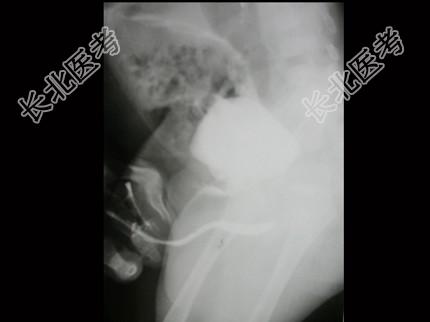

- 单项选择题男,4个月, 阴茎、排尿异常4个月,行尿道造影如图所示, 最可能的诊断是 ( )

A、正常尿道

B、尿道瓣膜形成

C、尿道下裂畸形

D、尿道憩室

E、尿道重复畸形